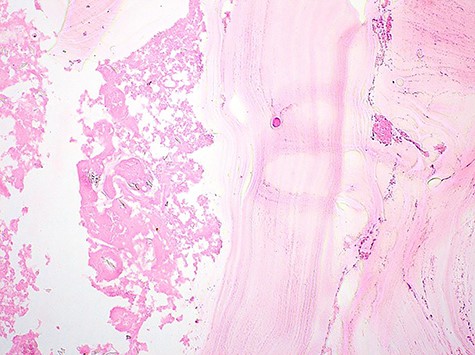

Anatomo-pathological examination revealed presence of a multilocular renal cystic lesion containing many hyaline acellular membranes. The cystic layer was made of a fibrotic tissue contain many inflammatory cells with cholesterol clefts (Figs 3 and 4).

Pathological examination revealed presence of a laminated; acellular and eosinophilic membrane with presence of many scolexes in the cystic lumen. (HE; 100X).